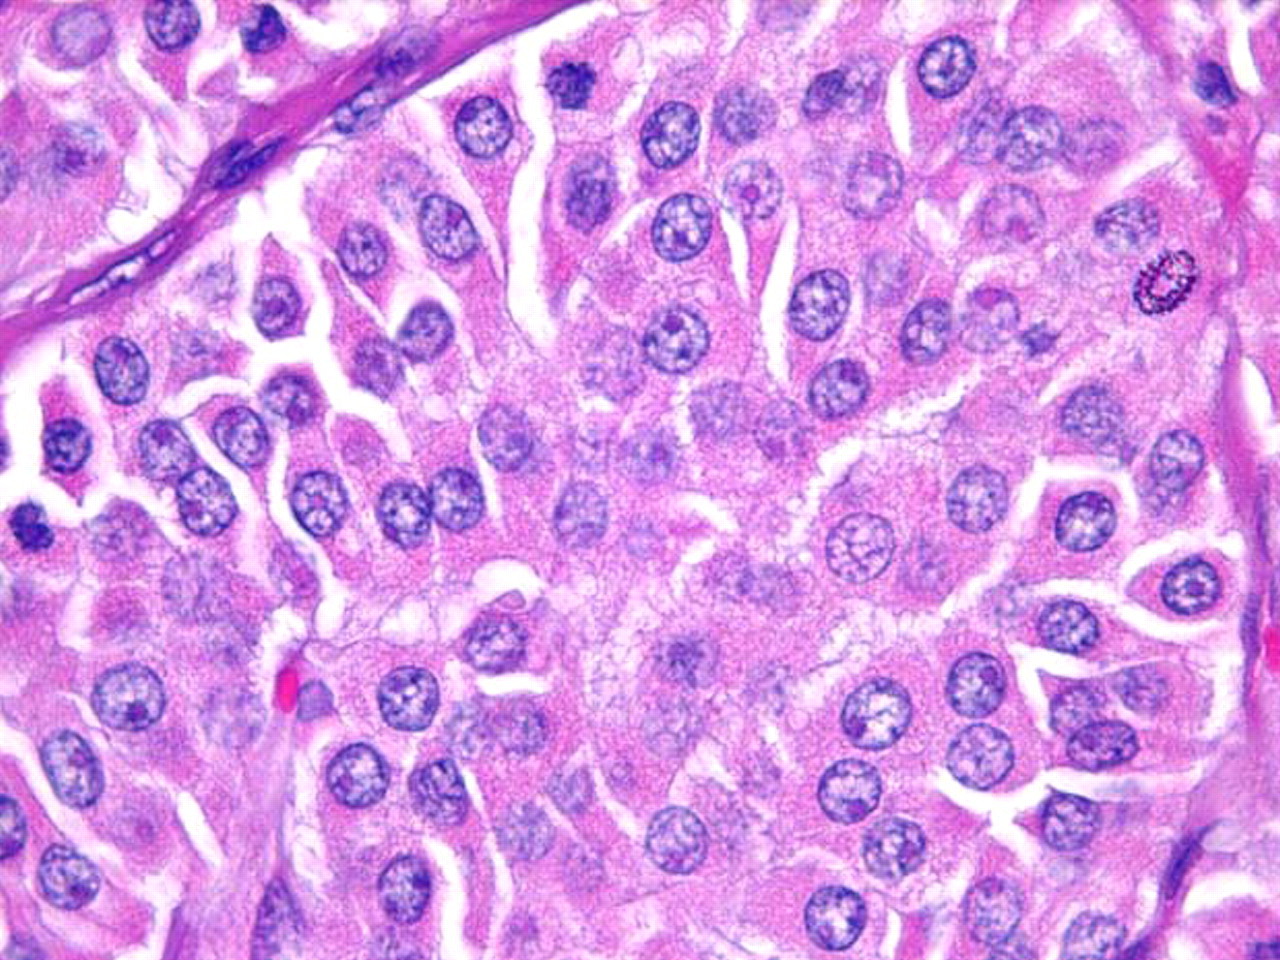

Oncocytic cells (previously known as Hürthle cells) with abundant granular, eosinophilic cytoplasm and ‘cherry pink’ nucleoli

Sandoval MAS et al. Case Reports 2011;2011:bcr1120103536; used with permission